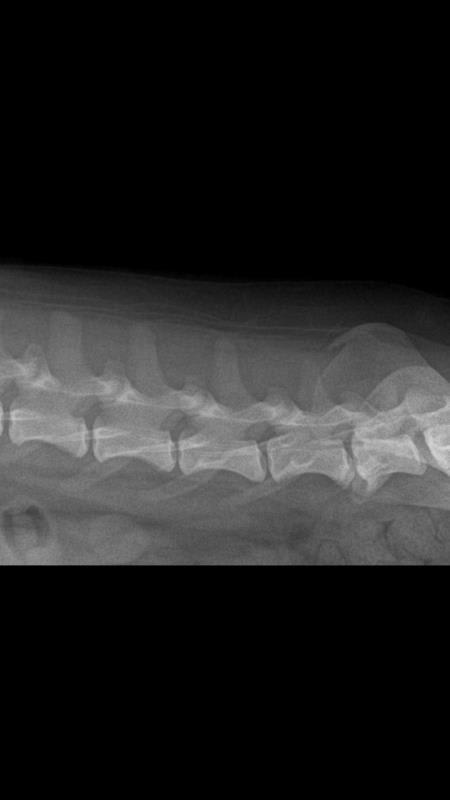

My dog Bean is nearly 8 years old and feels pain when we touch him recently. I found him lying on the ground all the time. I took him to the vet he told me Bean is suffering from bone spurs. Here is his CT. We gave him Previcox and he is now getting much better, wanting to play with us. I’m wondering is this a really bone spurs? How should I treat him?

I see an x-ray and not a CT, but this does show signs of spondylosis deformans in the vertebrae. A way to describe the arthritic changes in the bone is to call it bone spurs, so I agree with the diagnosis. The fact that the Previcox made him feel better is good evidence that the correct diagnosis was made and appropriately treated. Considering this, I recommend continuing to follow the treatment plan that your veterinarian gave. Below is a link to more information about this condition. https://vcahospitals.com/know-your-pet/spondylosis-deformans-in-dogs